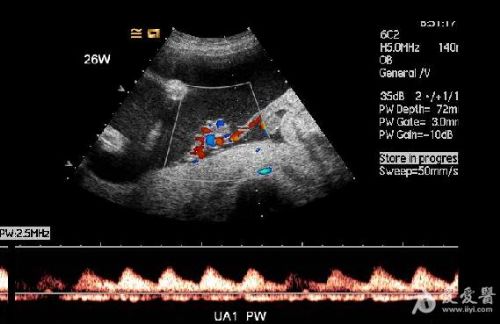

1.CDFI未见异常胎儿心脏显示,但胎体内可见血液流动。

2.无心畸胎的脐带为单脐动脉,PW显示为入胎动脉血流,其血流频谱所显示的心率、心律与正常胎儿的心率、心律完全一致。但其脐动脉的阻力指数明显低于正常胎儿。说明异常胎儿的血供完全来自于正常胎儿心脏的“泵”。

6、频谱及彩色多普勒血流显像可显示无心畸胎脐动脉及脐静脉内血流方向与正常胎儿相反,无心畸胎脐动脉血流从胎盘流向胎儿髂内动脉达胎儿全身,脐静脉血流从胎儿脐部流向胎盘,正好与正常胎儿脐动脉、脐静脉血流方向相反。

1.无心畸胎序列征CDFI可显示胎体内有血液流动,其脐带内有血流信号。而死胎胎体及脐带内无血流显示。